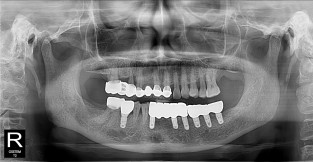

• 11

하악

치료기간 : 2021-11-30 ~ 2022-07-13

1. 상기 x-ray 이미지 모두 동일한 해당 의료기관에서 진료한 환자입니다.

2. 상기 x-ray 이미지 모두 동일 인물의 것입니다.

3. 치료 전 이미지는 2021-11-30에 촬영했으며, 치료 후 이미지는 2022-07-13에 촬영하였습니다.

4. 상기 x-ray 이미지 모두 동일 조건에서 환자분의 동의를 받아촬영되었습니다.

* 임플란트 시술은 환자분의 상태(고혈압, 당뇨 등)에 따라 부작용이 있을 수 있으니, 반드시 전문의와 상담이 필요합니다.

* 임플란트 수술 부작용

: 수술 후 출혈, 교합, 통증, 붓기, 염증 등의 문제점이 발생할 수 있습니다.)